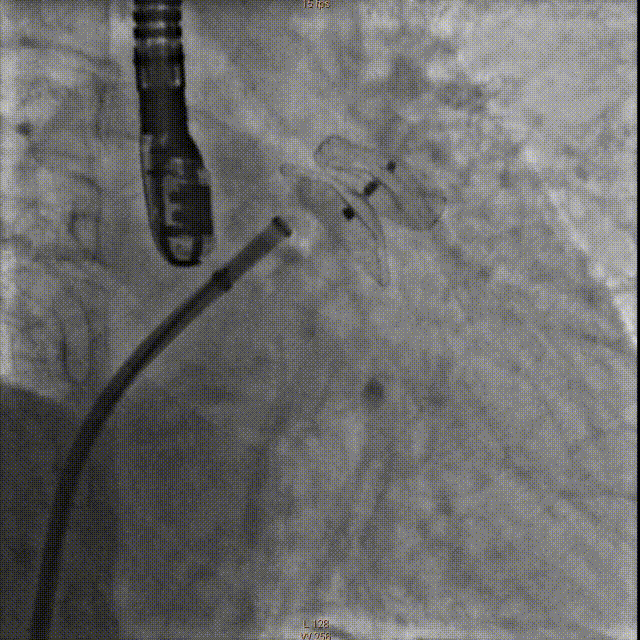

LAA造影

交换右侧8F动脉鞘及加硬钢丝换入1个8F Swartz L1长鞘至上腔静脉口,经Swartz鞘送房间隔穿刺针于PA位及RAO45°及食道超声精确定位房间隔后下位置行穿刺房间隔成功后,交换加硬钢丝至左上腔静脉,置入左心耳封堵器传输外鞘,通过外鞘送入5F猪尾巴导管至左心耳,测量左心房压力24/16mmHg,左心耳压力为25/11mmHg,行左心耳造影,测量左心耳形态及开口经线,左心耳形态为仙人掌状,DSA造影测量20/28mm。